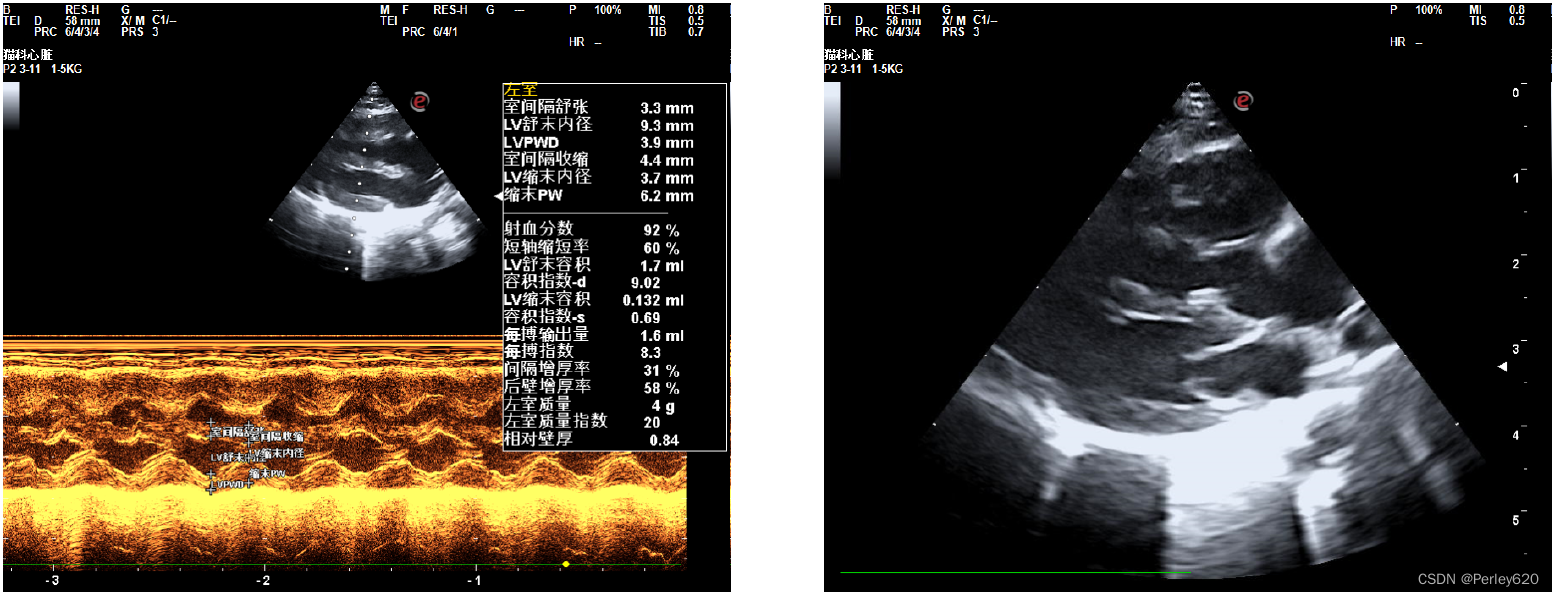

然后给她拍X光片,给她做彩超看心脏,宠物医院的院长看了半天,也没能确定是什么问题,她觉得是心脏左心室隔膜缺损,但没法给定论。

我们就去了宠物医院的总院,找了总院的院长做进一步的检查,最终是重度肺高压,就是很严重的一种病。

诊断的B超图